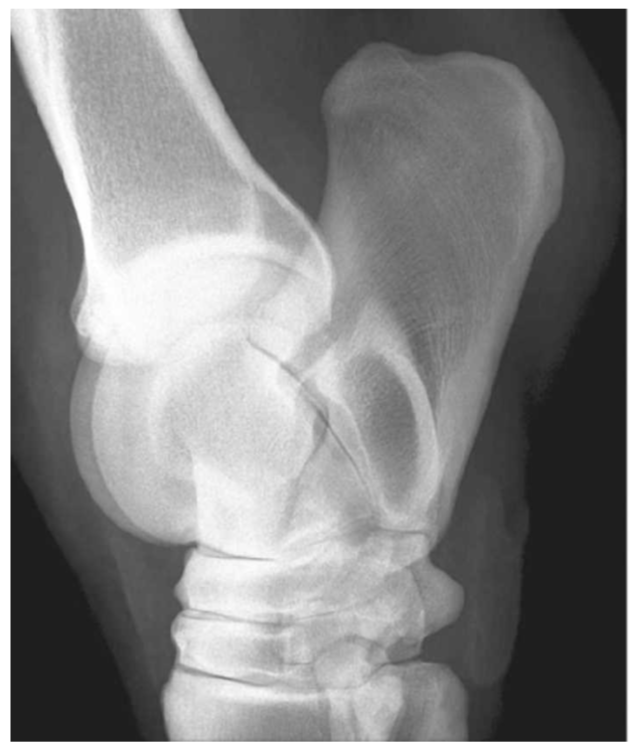

Appearance of the talocalcaneal joint on LM rads

Upside down Y shape